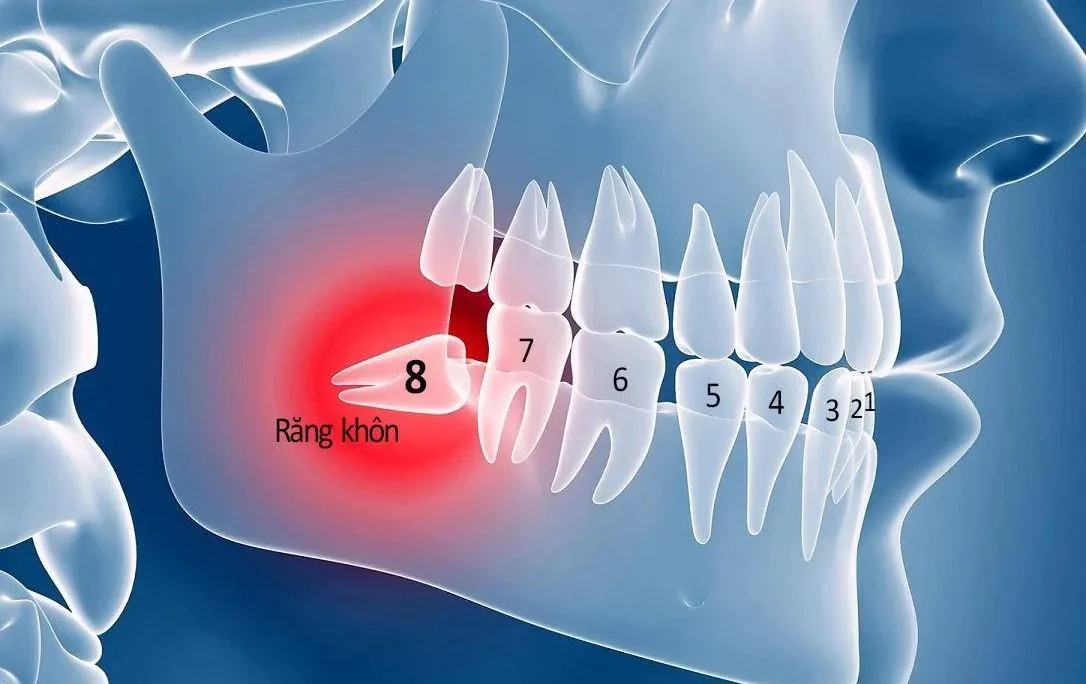

Răng khôn – chiếc răng cuối cùng trên cung hàm, thường gây ra nhiều phiền toái do mọc lệch, mọc ngầm hay bị đau nhức. Việc tìm

Răng khôn là chiếc răng mọc cuối cùng trên cung hàm, thường xuất hiện trong độ tuổi từ 17 – 25. Do mọc muộn khi xương hàm